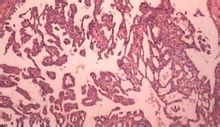

(二)鏡檢 瘤細胞異型性明顯,結構不一。有的呈實性團塊或小條索狀排列,有的可見腺腔形成,有的排列成管狀或腺樣結構。一般認為具有腺腔樣結構者,分化程度較高,惡性程度較低。小條索及小團塊之間的結締組織多少不定,多者與硬癌相似,間質少而癌細胞多者可稱軟癌。

常見的支氣管腺癌形成腺腔結構,腫瘤可以由分化好和分化差的成分混合存在。細胞內黏液需要通過特殊染色黏液卡紅染色或PAS染色來證實。另外乳頭狀或小管狀結構也可以見到,腺癌還可以有不常見結構:透明細胞、印戒細胞和梭形細胞。病理上腺癌必須與間皮瘤相鑑別。這一點對於細胞學標本來說很困難,而且需要其他輔助的方法幫助才能準確分型。

腺癌細胞與鱗狀細胞癌或大細胞癌相比,更加相對一致。細胞較大,核較大,核漿比值較高,有明顯的嗜酸性核仁。胞漿內可見空泡,說明有黏液產生。與鱗狀細胞癌不同,細胞的界限不清楚。組織學分級有分化好、中等分化或分化差三個級別,大多數為中等分化。腺癌一般不需要做免疫組化就能確診,但在區分原發、轉移或間皮瘤時需要做免疫組化。